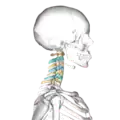

Illustration of cervical vertebrae

Shape of cervical vertebrae (shown in blue and yellow). Animation.

Cervical vertebrae, lateral view (shown in blue and yellow)